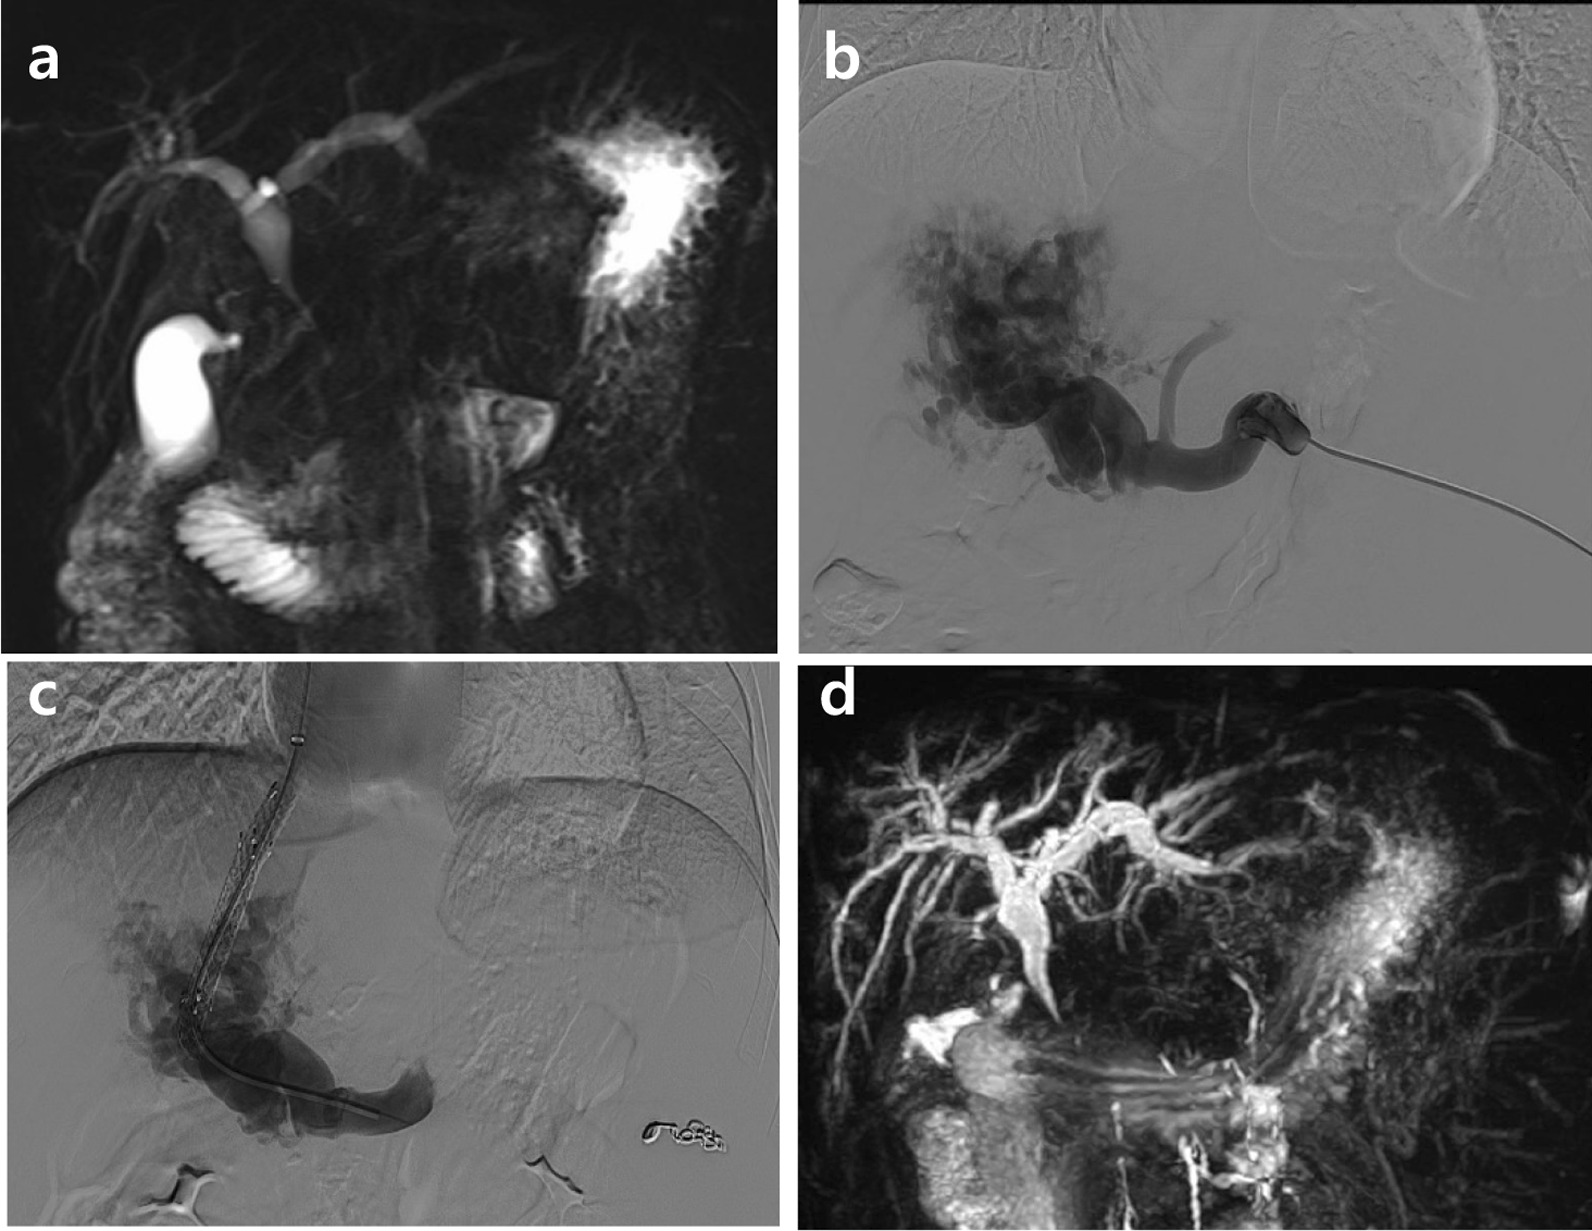

A 23-year-old man with liver cirrhosis presented with jaundice for one month. The initial laboratory test indicated total bilirubin (TB) of 4.81 mg/dL, direct bilirubin (DB) of 4.44 mg/dL, alanine aminotransferase of 268 U/L, aspartate aminotransferase of 128 U/L, alkaline phosphatase(ALP) of 1105 U/L, and gamma-glutamyl transferase (GGT) of 1018 U/L. Child–Pugh’s classification was graded as A. Gastroscopy showed moderate esophageal and gastric varices. Magnetic resonance cholangiopancreatography (MRCP) showed multiple tortuous hepatopetal collateral vessels compressing the common bile duct (CBD) and leading to the dilated proximal bile duct (Fig. 1a). TIPS was considered as alternative approach to decrease portal venous pressure and alleviate bile obstruction. The main trunk and intrahepatic branches of portal vein were completely occluded and replaced by collaterals. Most collaterals were small, torturous and not suitable for TIPS placement. Traditional TIPS based on cross-sectional images may not guarantee that the suitable collateral was punctured. Therefore, a guidewire was inserted into the appropriate collateral vessel through transsplenic approach to guide intrahepatic puncture to ensure a linear intrahepatic shunt (Fig. 1b). Once the collateral vein was accessed successfully, indirect portography was performed. The intrahepatic tract was dilated using a balloon catheter to allow the implantation of an 8 mm × 60 mm expanded polytetrafluoroethylene covered stent. The portosystemic pressure gradient decreased from 24 to 13 mmHg and an 6 mm coil was used to embolize the splenic access after withdrawal of the sheath (Fig. 1c). Three months after the operation, TB dropped to 2.23 mg/dL, DB to 1.39 mg/dL, ALP to 504 U/L and GGT to 670 U/L. A follow-up MRCP revealed that the biliary obstruction was alleviated (Fig. 1d). In addition, the patient showed no jaundice.